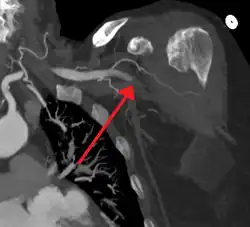

![]() | |

| Acute embolism to the right femoral artery resulting in ischemia | |